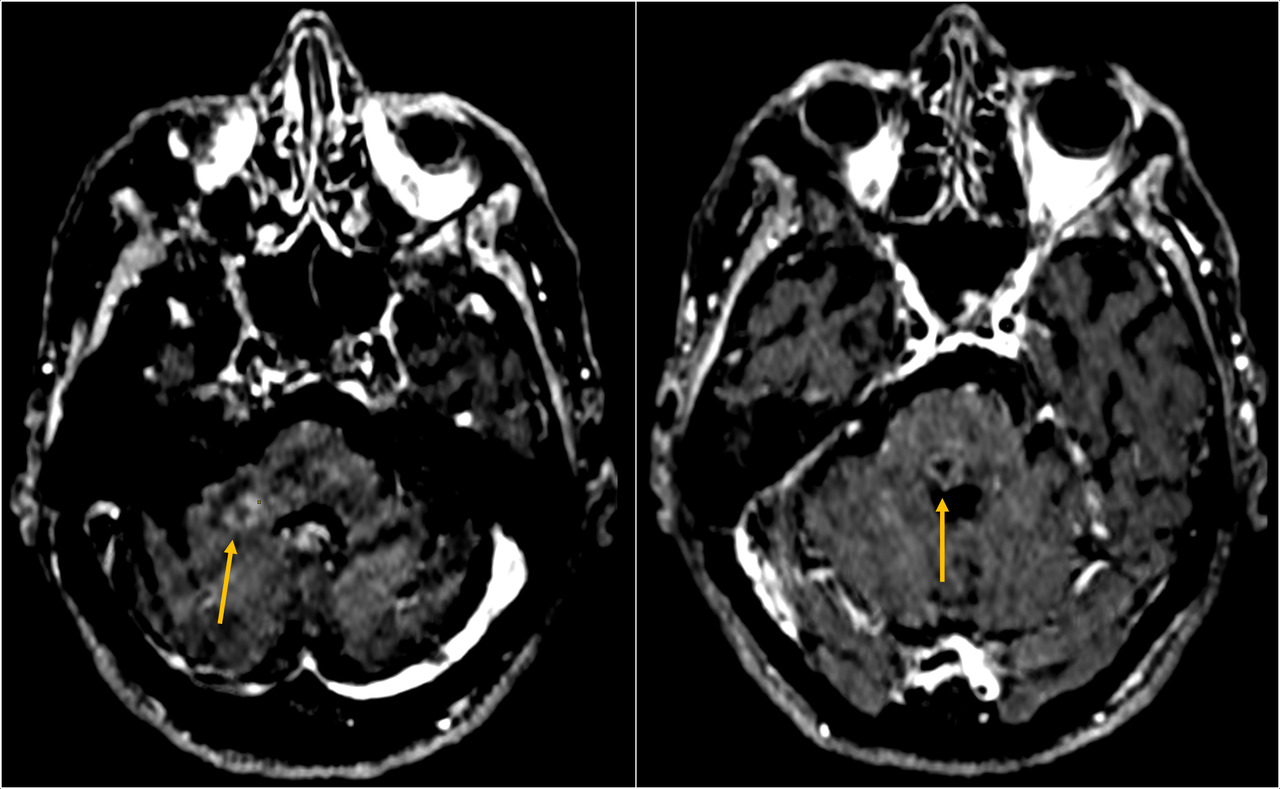

Une patiente âgée de 90 ans vivant seule chez elle, avec la visite d’aides à domicile, est hospitalisée pour une asthénie sévère associée à un syndrome confusionnel fébrile évoluant depuis quelques jours, sans point d’appel clinique. Elle est en bon état général et est sous valsartan pour une hypertension artérielle. L’examen clinique ne retrouve aucune anomalie en dehors d’une confusion fébrile sans syndrome méningé ni signe de localisation. Les hémocultures sont stériles. La protéine C-réactive (CRP) est à 126 mg, avec une hyperleucocytose à polynucléaires neutrophiles à 13 000/mm3. Le reste du bilan biologique est normal. Une ponction lombaire est réalisée en urgence  ; elle montre un liquide céphalorachidien (LCR) citrin (fig. 1) avec une protéinorachie à 3,29 g/L, une hypoglycorachie à 450 leucocytes/mm3 (36 % de polynucléaires, 75  % de lymphocytes). L’examen direct du LCR révèle des bacilles à Gram positif et la culture confirme l’identification de Listeria monocytogenes sensible à l’amoxicilline et au cotrimoxazole.  Dès les résultats de la ponction lombaire, la patiente a été mise sous amoxicilline à la dose de 200 mg/kg/24 h et de la gentamicine à 5 mg/kg/24 h a été ajoutée pour cinq jours. L’imagerie par résonance magnétique (IRM) [fig. 2] met en évidence plusieurs abcès (protubérance, cervelet) et une ventriculite bilatérale avec pus intraventriculaire (fig. 3). La patiente n’était pas immunodéprimée. La déclaration obligatoire a été effectuée. L’enquête de l’agence régionale de santé (ARS) n’a pas retrouvé de cas groupés dans l’entourage. Après six semaines d’antibiothérapie par amoxicilline intraveineuse à haute dose, la patiente a recouvré une conscience normale, sans séquelle neurologique clinique apparente, et une autonomie qui ont permis le retour à domicile.

La localisation méningée1,2 est associée dans près de la moitié des cas à des signes d’encéphalite diffuse avec des abcès intracérébraux localisés de façon prédo­minante au rhombencéphale. Des abcès nécrotiques coalescents et multiples apparaissent, entraînant des pertes de substances importantes du tissu nerveux.